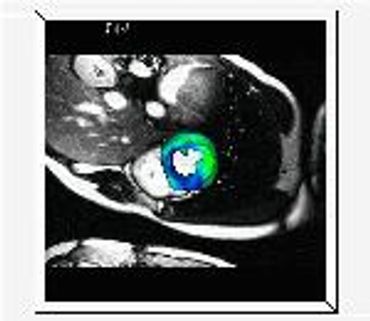

Procesamiento de Imágenes Vectoriales y 4D MRI - Medical Image Analysis (MIA99) (pdf)

DescargarEcocardiografía 3D+T- Transactions on Medical Imaging (TMI02) (pdf)

TODOS LOS CÁLCULOS, IMÁGENES Y ANIMACIONES en esta página y artículos, fueron producidos con PROGRAMAS ESCRITOS POR MI en C / C++ y VTK/TCL/TK